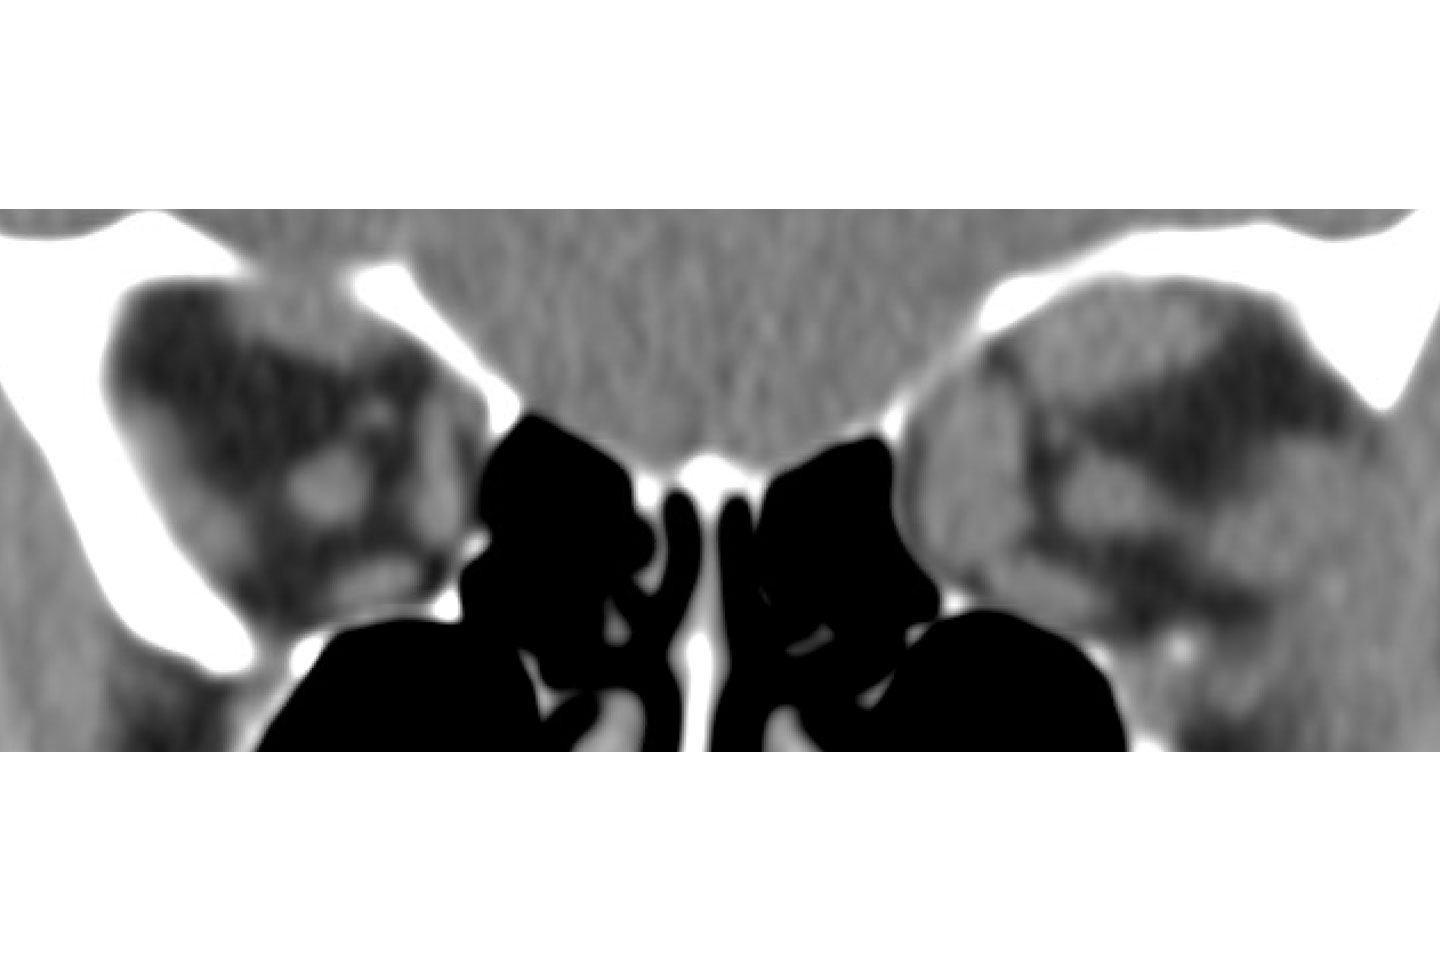

Coronal preoperative orbital imaging showing crowding of left orbital contents. Source: NYU Langone Health

Coronal postoperative imaging showing relief of orbital pressure. Source: NYU Langone Health